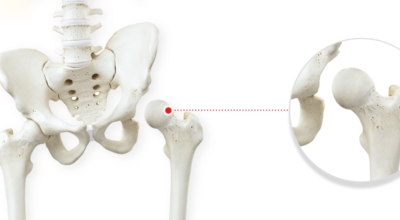

앞뒤로 움직이는 무릎 관절과는 다르게 고관절은 앞뒤 뿐만 아니라 좌우, 회전 등 자유롭게 움직임이 가능하며 운동 범위가 큰것이 특징입니다. 우리 몸 중 가장 큰 관절이기도 하다. 고관절에서 발생할 수 있는 고관절 통증 증상에 대해 알아보겠습니다.